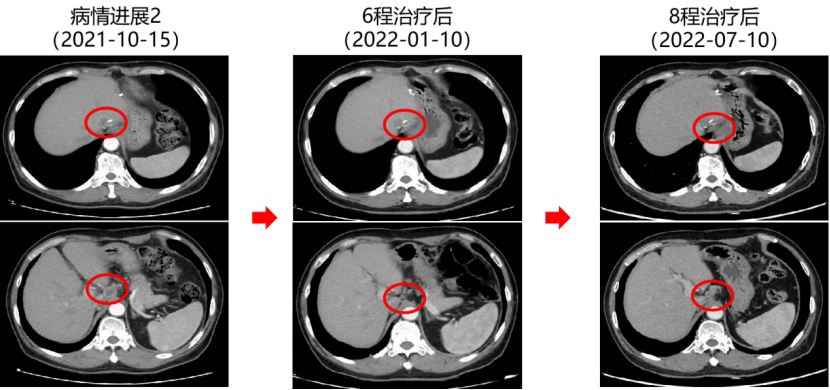

二 病例分享 专家简介 01 基本情况 患者:汪XX,男,63岁。身高 165cm;体重 65kg;体表面积 1.70m2;ECOG 1分。 主诉:反复解黏液血便3天。 对磁共振造影剂过敏,无食物、其他药物过敏史。既往史、个人史、婚育史、家族史均无特殊,无吸烟、饮酒史。 02 初诊病史 现病史:患者2017年3月初无明显诱因下解黏液血便,量中等,为鲜血,反复发作,无恶心、呕血、黑便、腹痛、腹泻、里急后重等不适。遂于2017年3月初就诊我院。 胸、腹、盆腔CT平扫+增强:乙状结肠肠壁明显增厚,肠腔狭窄,增强期强化明显;肝脏多发低密度病灶,增强期不规则强化,考虑乙状结肠癌伴肝脏多发转移。 03 治疗方案 【一线治疗】 2017-06-22 西妥昔单抗+FOLFIRI* Q2W×3 西妥昔单抗 900mg ivgtt D1; 5-氟尿嘧啶 0.6g iv D1,3.5g civ 48h; 亚叶酸钙 0.6g ivgtt D1; 伊立替康 280mg ivgtt D1。 第1疗程结束后黏液血便较前消失,过程顺利,耐受良好,无皮疹、腹泻等不良反应,治疗10疗程,疾病进展。 疗效评估-影像学(部分缓解,PR)。 2017-07-15 乙状结肠癌切除术* 手术记录:肿瘤位于乙状结肠,大小约4cm×3cm,未突破浆膜层,病灶周围可及数个稍肿大淋巴结,未及盆底种植结节。 手术过程顺利,术后恢复良好。 术后病理:(乙状结肠)中分化腺癌,浸润肠壁浆膜下层,两切缘阴性,未见脉管癌栓及神经束侵犯,LN 2/18(+) 2017-08-20 肝转移瘤切除术* 手术记录:肝脏肿瘤位于肝右叶,大小分别约2cm×1.5cm,1cm×1.2cm,其余肝表面未见异常结节,腹腔无腹水、无粘连。 手术过程顺利,术后恢复良好。 术后病理:(肝右叶病灶)中分化腺癌,结合临床病史,符合乙状结肠癌肝转移,肝组织切缘未见癌。 疗效评估-影像学(NED)。 2017-11-06 西妥昔单抗+FOLFIRI* Q2W×3 西妥昔单抗 900mg ivgtt D1; 5-氟尿嘧啶 0.6g iv D1,3.5g civ 48h; 亚叶酸钙 0.6g ivgtt D1; 伊立替康 280mg ivgtt D1; 过程顺利,无皮疹、腹泻等不良反应。每疗程后均予PEG-CSF预防性升白,耐受良好。 疗效评估-影像学(病情进展,PD1)。 胸、腹、盆腔CT平扫+增强:肝左外叶低密度灶,增强期不规则强化,结合病史,考虑结肠癌肝转移,余未见明显异常。 【二线治疗】 2018-03-06 肝左外叶肿瘤切除术* 术中探查见:肿瘤位于肝左外叶,质硬,边界不清,余肝脏表面未见异常结节灶,腹盆腔无腹水。 手术过程顺利,术后恢复良好。 术后病理示:(肝左叶)中分化腺癌,结合临床病史,符合结肠腺癌肝转移。 2018-04至2018-07 卡培他滨+奥沙利铂* Q3W×5 卡培他滨 1.5g BID D1-14; 奥沙利铂 200mg ivgtt D1。 过程顺利、耐受良好,无腹泻、神经毒性等不良反应。 疗效评估-影像学(病情进展,PD2)。 胸、腹、盆腔CT平扫+增强:肝尾状叶结节状异常密度灶,增强期不规则强化,结合病史,考虑结肠癌肝转移,余未见明显异常。 2018-07至2020-04 贝伐珠单抗+卡培他滨* Q3W×21 贝伐珠单抗 500mg ivgtt D1; 卡培他滨 1.5g BID D1-14。 过程顺利、耐受良好,期间曾出现II度腹泻,对症治疗后可恢复正常。无血压升高、出血、蛋白尿、手足皮肤反应。 疗效评估-影像学(最佳疗效,PR)。 疗效评估-影像学(病情进展,PD3)。 腹腔镜肝尾状叶切除术+腹腔粘连松解术* 术中探查见:肿瘤位于肝尾状叶,质硬,边界不清,余肝脏表面未见异常结节灶,腹盆腔无腹水。 手术过程顺利,术后恢复良好。 术后病理示:(肝尾状叶)中分化腺癌,结合临床病史,符合结肠腺癌肝转移。 2020-06至2021-09 贝伐珠单抗+卡培他滨* Q3W×16 贝伐珠单抗 500mg ivgtt D1; 卡培他滨 1.5g BID D1-14。 过程顺利、耐受良好,期间曾出现II度腹泻,对症治疗后可恢复正常。无血压升高、出血、蛋白尿、手足皮肤反应。 疗效评估-影像学(NED)。 疗效评估-影像学(NED)。 【三线治疗】 2021-12-16 西妥昔单抗+TAS-102* Q3-4W×2 西妥昔单抗 900mg ivgtt D1; TAS-102 60mg BID D1-5,8-12。 过程顺利、耐受稍差,期间出现II度骨髓抑制(三系减少),对症治疗后可恢复正常。无皮疹、输液反应等。 疗效评估-影像学(部分缓解,PR)。 04 治疗小结